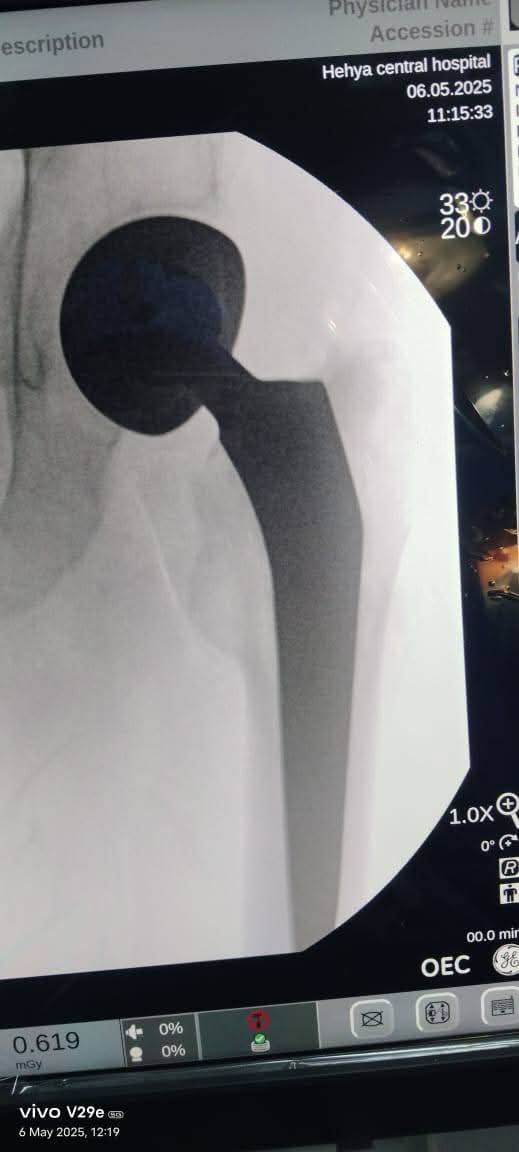

أطباء مستشفى ههيا المركزي ينجحون في إجراء جراحة دقيقة لتركيب مفصل الفخذ لإنفاذ مريض من الإعاقة

نجح الفريق الطبي بقسم العظام بقيادة الدكتور شريف عبدالمنعم رئيس قسم العظام بمستشفى ههيا المركزي، وبمشاركة الدكتور محمود عبد العزيز طبيب العظام، والدكتور محمد زعزوع أخصائي التخدير، وتحت إشراف الدكتورة هبة الضريبي مديرة المستشفى، في إجراء جراحة دقيقة لتركيب مفصل صناعي لمريض يبلغ من العمر ٦٥ عامًا، كان يعاني من كسر بعنق عظمة الفخذ الأيمن.